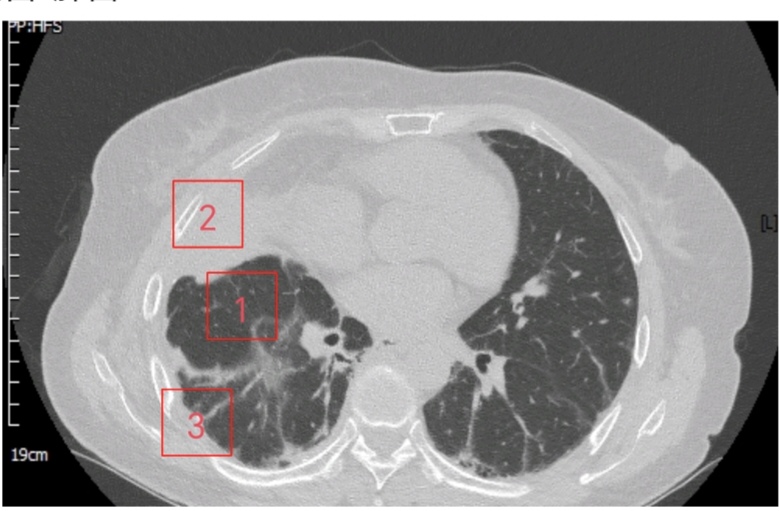

▲闭式引流前

▲闭式引流后